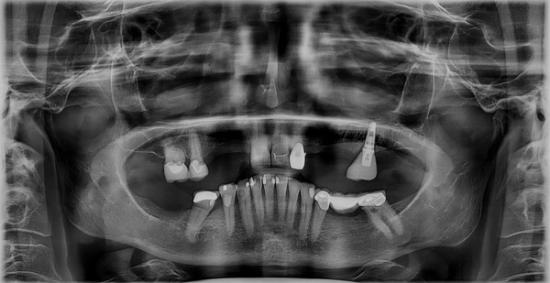

Before Photo